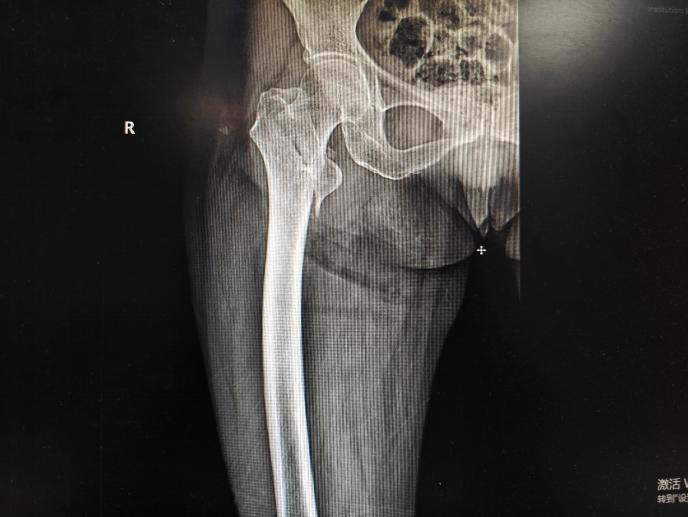

此次手术为女性患者,89岁,入院前1日因跌倒导致右股骨粗隆间骨折合并右桡骨远端粉碎性骨折,症状为右下肢及右腕关节肿胀、畸形伴活动受限,严重影响日常生活,保守治疗卧床时间长且效果不佳。患者既往身体较差,患有冠状动脉粥样硬化性心脏病、心律失常(房性早搏合并室性早搏)、高血压(2级,极高危)、脑梗死后遗症,患者前往多家医院诊治,均因患者的全身情况对于手术是一个巨大挑战而被婉拒。

患者股骨粗隆间骨折

股骨粗隆间骨折

随着老龄化人口的增加,股骨粗隆间骨折高龄患者逐年上升,因为高龄,常合并多种基础疾病,经常被人称为“人生最后一次骨折”。目前临床上多采取尽早髓内钉手术微创治疗,但若患者身体条件较差,不能耐受麻醉,过去对于这种情况,往往采取骨牵引、皮牵引、“丁”字鞋登等保守治疗手段,卧床时间长,并发症较高。目前针对这种情况,出现了新型固定方式(股骨粗隆外固定架),手术采取局麻手段最大限度降低患者麻醉风险,手术时间短,出血少,固定可靠,患者可以早期活动,最大限度的减少卧床并发症。